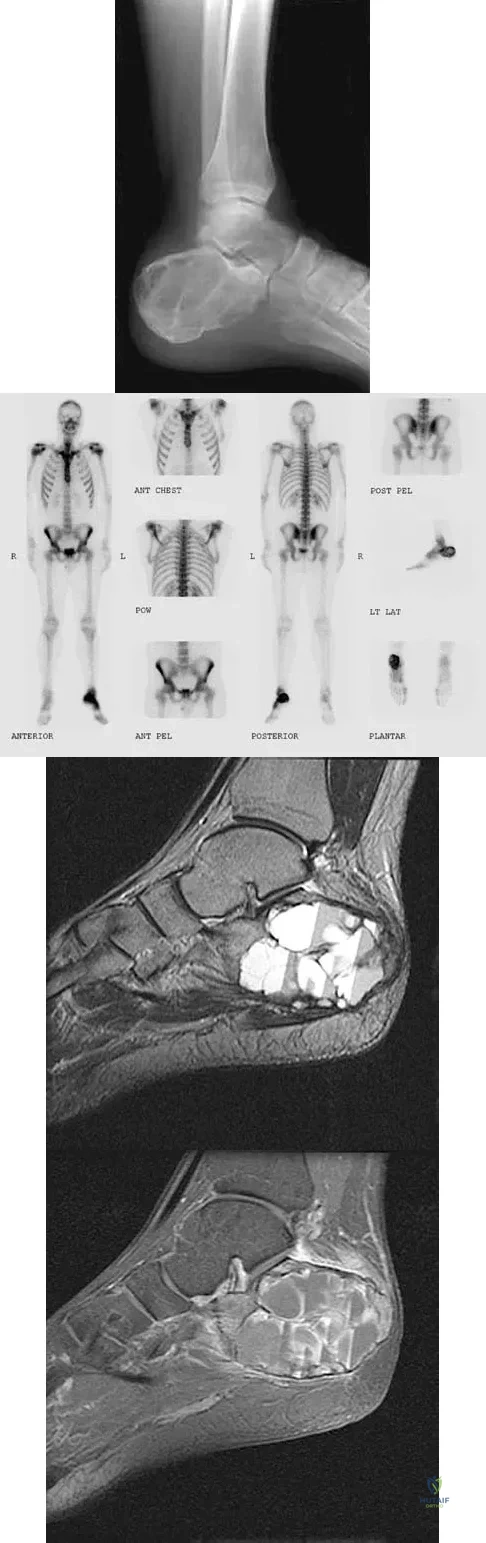

A 23-year-old man has had heel pain and fullness for the past several months. He reports that initially the pain was present only with activity, but more recently the pain has become constant. Figures 53a through 53d show a radiograph, a bone scan, and T2-weighted and gadolinium MRI scans. What is the most likely diagnosis?